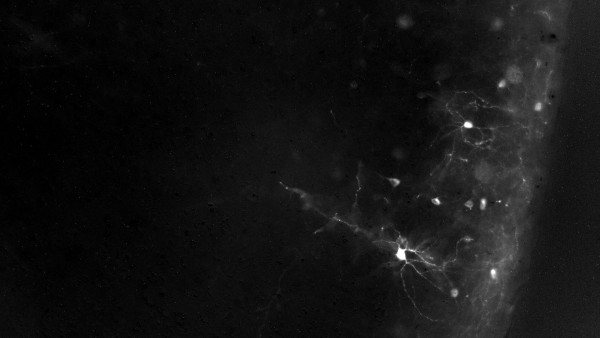

Brain imaging from Dr. Head's work at University of Minnesota Department of Neuroscience, where he successfully modulated neuronal activity to accelerate learning and memory in his preclinical work, using optogenetic techniques. He will now further develop neuromodulation for non-invasive human applications (photo supplied).